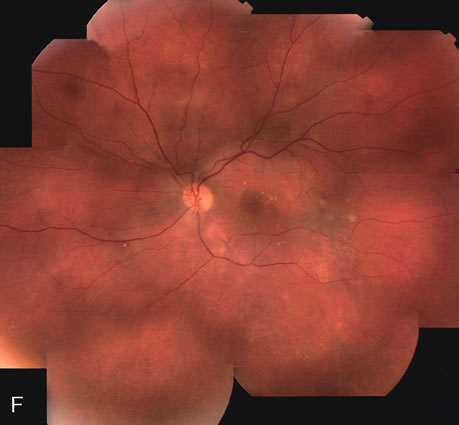

Clinically discernible peripheral dependent bullous neurosensory detachments have been described in patients with chronic CSC.85–92 Yannuzzi and co-workers first characterized the presence of RPE atrophic tracts extending inferiorly in the fundus periphery secondary to antecedent retinal detachment in patients with CSC.85 Presumably, there is a particularly severe and/or longstanding leakage of fluid from an RPE defect in the subretinal space at the posterior pole. The subretinal fluid gravitates inferiorly to form a dependent neurosensory detachment in a “flask,” “teardrop,” “dumbbell,” or “hourglass” pattern (Fig. 31). Sometimes the tract of subretinal fluid connecting the macular detachment with the bullous neurosensory detachment in the inferior hemisphere is so shallow that it is very difficult to appreciate. The RPE under the chronic retinal detachment experiences atrophic changes that appear as atrophic RPE tracts connecting the posterior pole with the dependent retinal detachment. The retina itself develops secondary manifestations including pigment migration, capillary dilatation (telangiectasia) proximally and capillary nonperfusion (ischemia) distally to the area of detached retina (see Fig. 31). The changes in the RPE consist of both RPE atrophy and pigment clumping in the form of perivascular deposits or bone spicules, a condition described by Gass as a “pseudoretinitis pigmentosa–like atypical CSC presentation.”87

Other complications noted in these patients are cystoid macular edema or, more frequently, cystoid retinal changes in the areas of chronic detachment, subretinal lipid deposition, choriocapillaris atrophy secondary to the RPE damage in the areas of RPE tracts, and CNV.89,90,204–206 This severe variant of CSC appears to be more frequent in patients of Latin or Asian ancestry, and it is usually associated with frequent recurrences, permanent central vision loss, and significant superior visual field loss. |